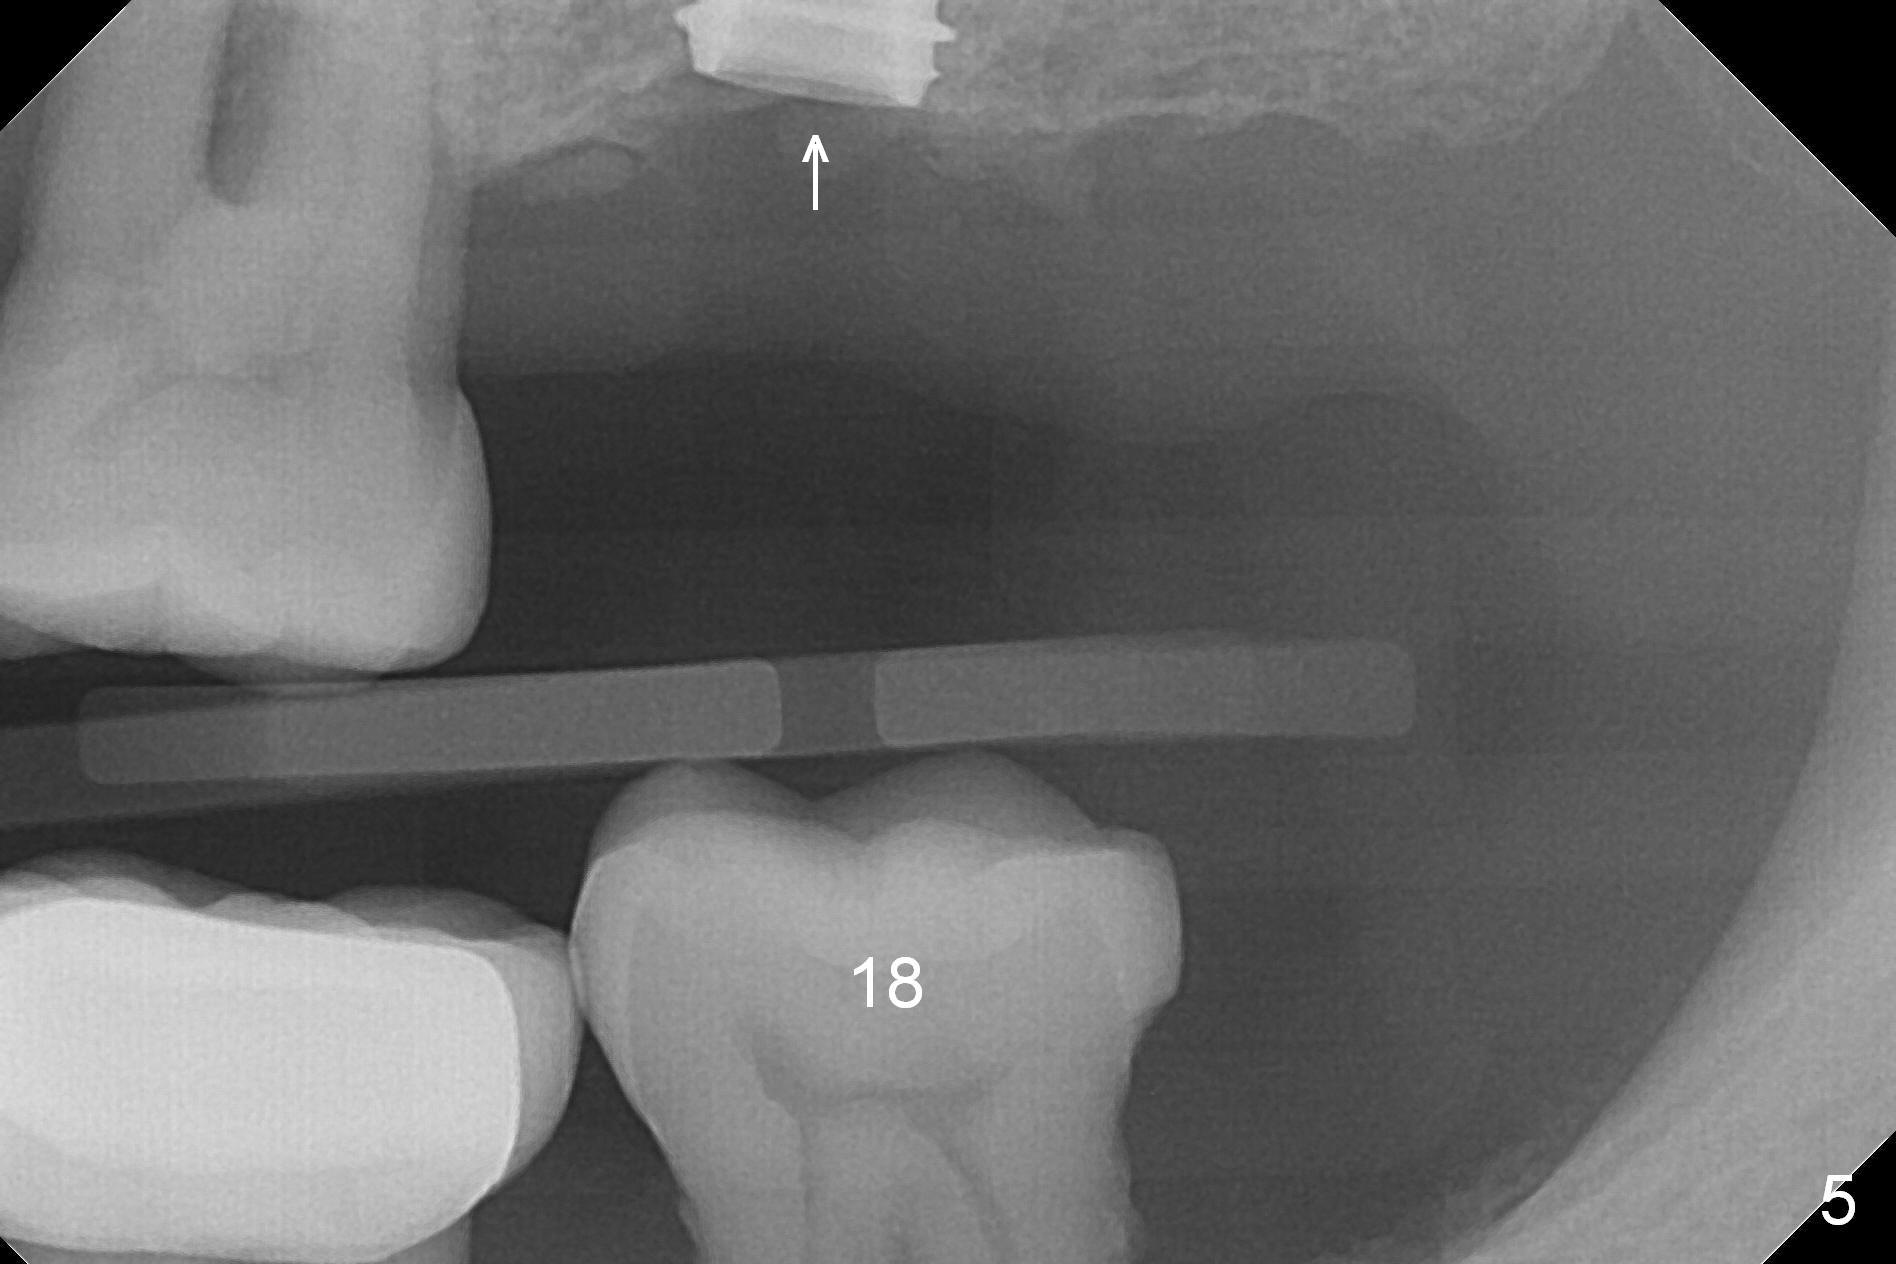

A 1.2 mm initial drill is used to start osteotomy at the site of #15 (Fig.1). After moving the osteotomy distally (with Lindamann bur), the osteotomy is enlarged by DIO Bone Expanders until 2.4/3.7 mm for 18 mm (gingival level) (Fig.2). Following the expander 3.0/4.4 mm, a 5x13 mm UF implant is placed supracrestal (Fig.3,4). After deepening the osteotomy with 3.8 mm drill for 3 mm, the implant is placed deeper by ~ 2 mm (Fig.5 arrow). Since the tooth #18 is supraerupted, a healing abutment (5.5x12(3) mm) is placed (Fig.6: H); the gingiva adapts to the abutment well. Suture is not necessary. The bone remains stable 2 and 4.5 months postop (Fig.7,8). Impression is taken. A crown is delivered nearly 6 months postop (08/07/2017). While there is minimal bone loss at #13 and 15 three years and 4 months post cementation, the tooth #14 and 18 are mobile (Fig.13,14, #13).